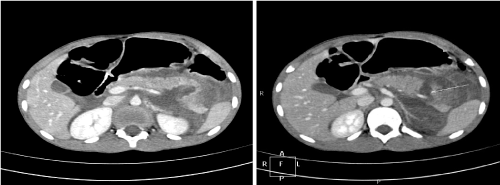

A CT abdomen in patient 1 showed a grade III pancreatic injury (full thickness laceration through body and tail of the pancreas) with extensive peripancreatic, intra-abdominal and pelvic free fluid (Figure 1). Splenic vessels and all other intra-abdominal organs were intact.

Figure 1. Extensive peripancreatic, intra-abdominal and pelvic free fluid